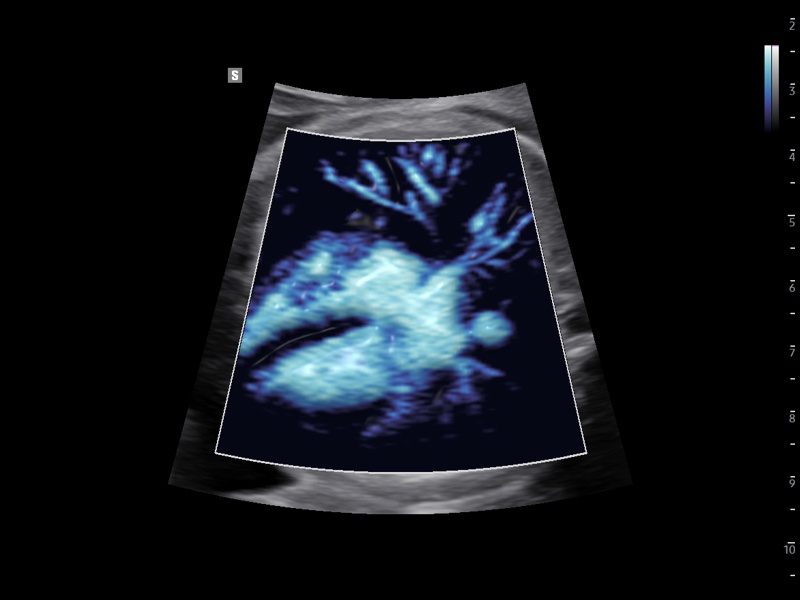

Fetal heart, MV-Flow™

Fetal heart, MV-Flow™ (echogramm №932)

[RU] Ultrasound image №932: Fetal heart in MV-Flow™ mode.

Echogramm was received by ultrasound scanner Z20 (new model).